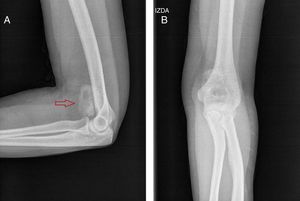

Mujer de 36 años, en seguimiento por tumoración dolorosa y progresiva en cara antero-medial del codo izquierdo e impotencia funcional, de 2 meses de evolución, resistente al tratamiento analgésico. Refería antecedente traumático previo, siendo diagnosticada de rotura fibrilar muscular. Ante la persistencia del cuadro, se realizó RMN ambulatoria, que sospechó un sarcoma de partes blandas, ingresándose para estudio de extensión. Los estudios de laboratorio y TC toraco-abdominal fueron negativos. Mediante gammagrafía ósea en 2 fases (figs. 1A y B), se demostró un área de captación heterogénea en región anterior del codo izquierdo, sin hallazgos significativos a otros niveles. Se planteó diagnóstico diferencial entre sarcoma de partes blandas, condrosarcoma y osteocondroma con degeneración maligna. Finalmente, se decidió biopsia percutánea eco-guiada, cuyo resultado fue de tumoración mesenquimal sin caracteres de malignidad, estableciéndose el diagnóstico definitivo de miositis osificante. Se recomendó reposo, tratamiento antiinflamatorio y rehabilitación posterior. A los 3 meses, presentó mejoría clínica con disminución del dolor, flexión completa y extensión a 120°. El control por radiología simple (figs. 2A y B) y TC sin contraste (fig. 3) reveló una masa calcificada, compatible con el diagnóstico anatomo-patológico.